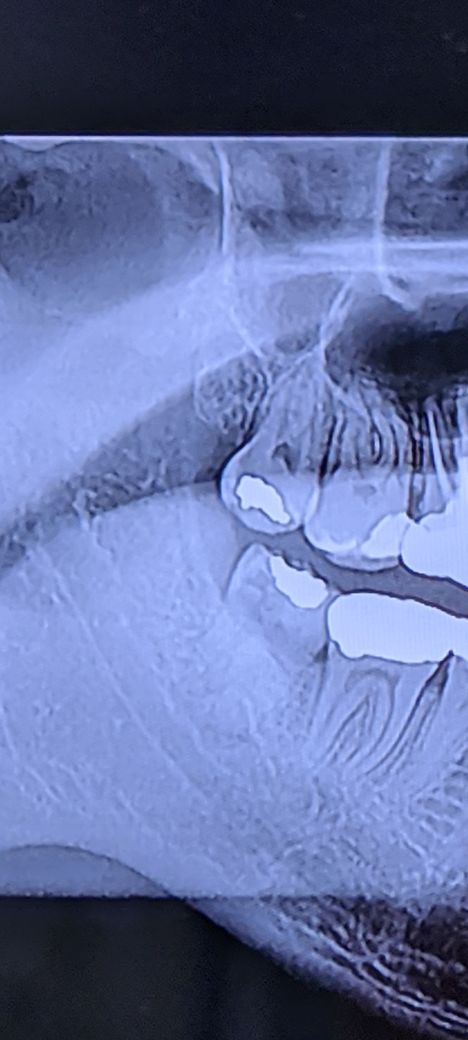

이런 사랑니면 신경 손상에 많이 주의해야 하나요?

아래 제일 안쪽 치아가 부러져서 치과에 갔더니 사랑니가 썪었다고 발치해야 한다고 하네요.

제가 뇌경색 환자라서 마비에 많이 민감해서요. 사랑니 발치 잘못하면 신경 손상으로 마비가 올 수 있다고 하더라구요. 당시 선생님은 딱히 그 부분에 대해서 말씀은 안하셨는데, 집에 와서 생각해보니 신경 손상이 겁이 나네요.

이정도면 좀 전문적인 치과로 가야 할만큼 위험할까요?

사랑니 발치시는 신경손상 위험성이 항상 존재 합니다. 단순 사랑니라서 크게 손상의 위험성은 없어 보이긴 합니다.

1. 마취나 발치 시 신경손상이 올 수는 있다고 설명은 하나 그건 가능성의 부분이고 확률은 높지 않으며, 일시적 신경손상이 있더라도 그 후 돌아오는 케이스가 많습니다.

2. 현재 사랑니의 경우 특별히 아래턱 신경과의 거리나 너무 가깝거나 그렇지는 않습니다.